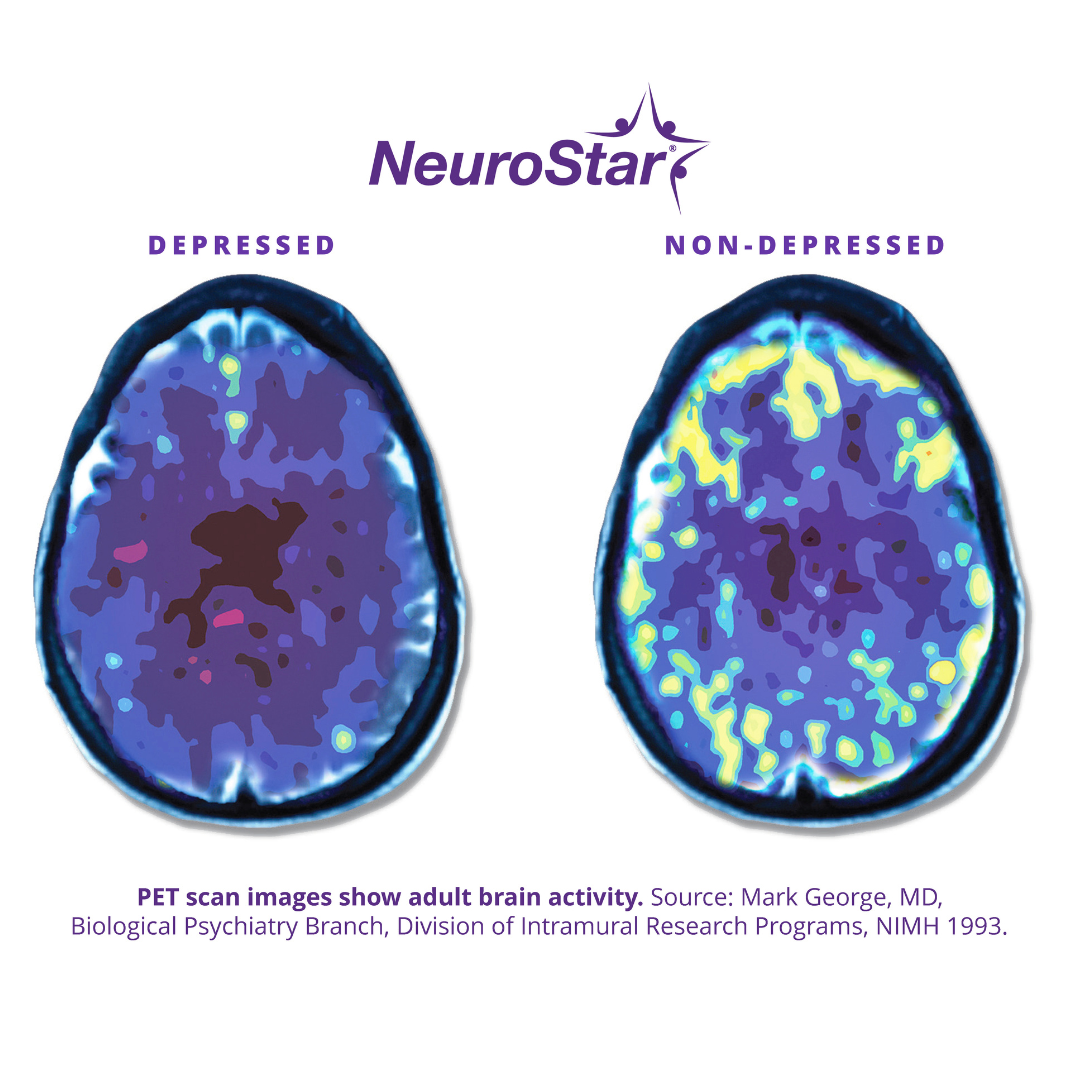

In a NeuroStar TMS session, a trained mental health provider places an electromagnetic coil against your scalp. The coil emits focused magnetic pulses that stimulate a part of the brain involved in mood regulation, especially the left dorsolateral prefrontal cortex, an area that may be underactive when someone is suffering from depression.